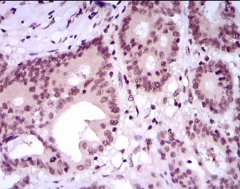

IHC    1/100 - 1/500